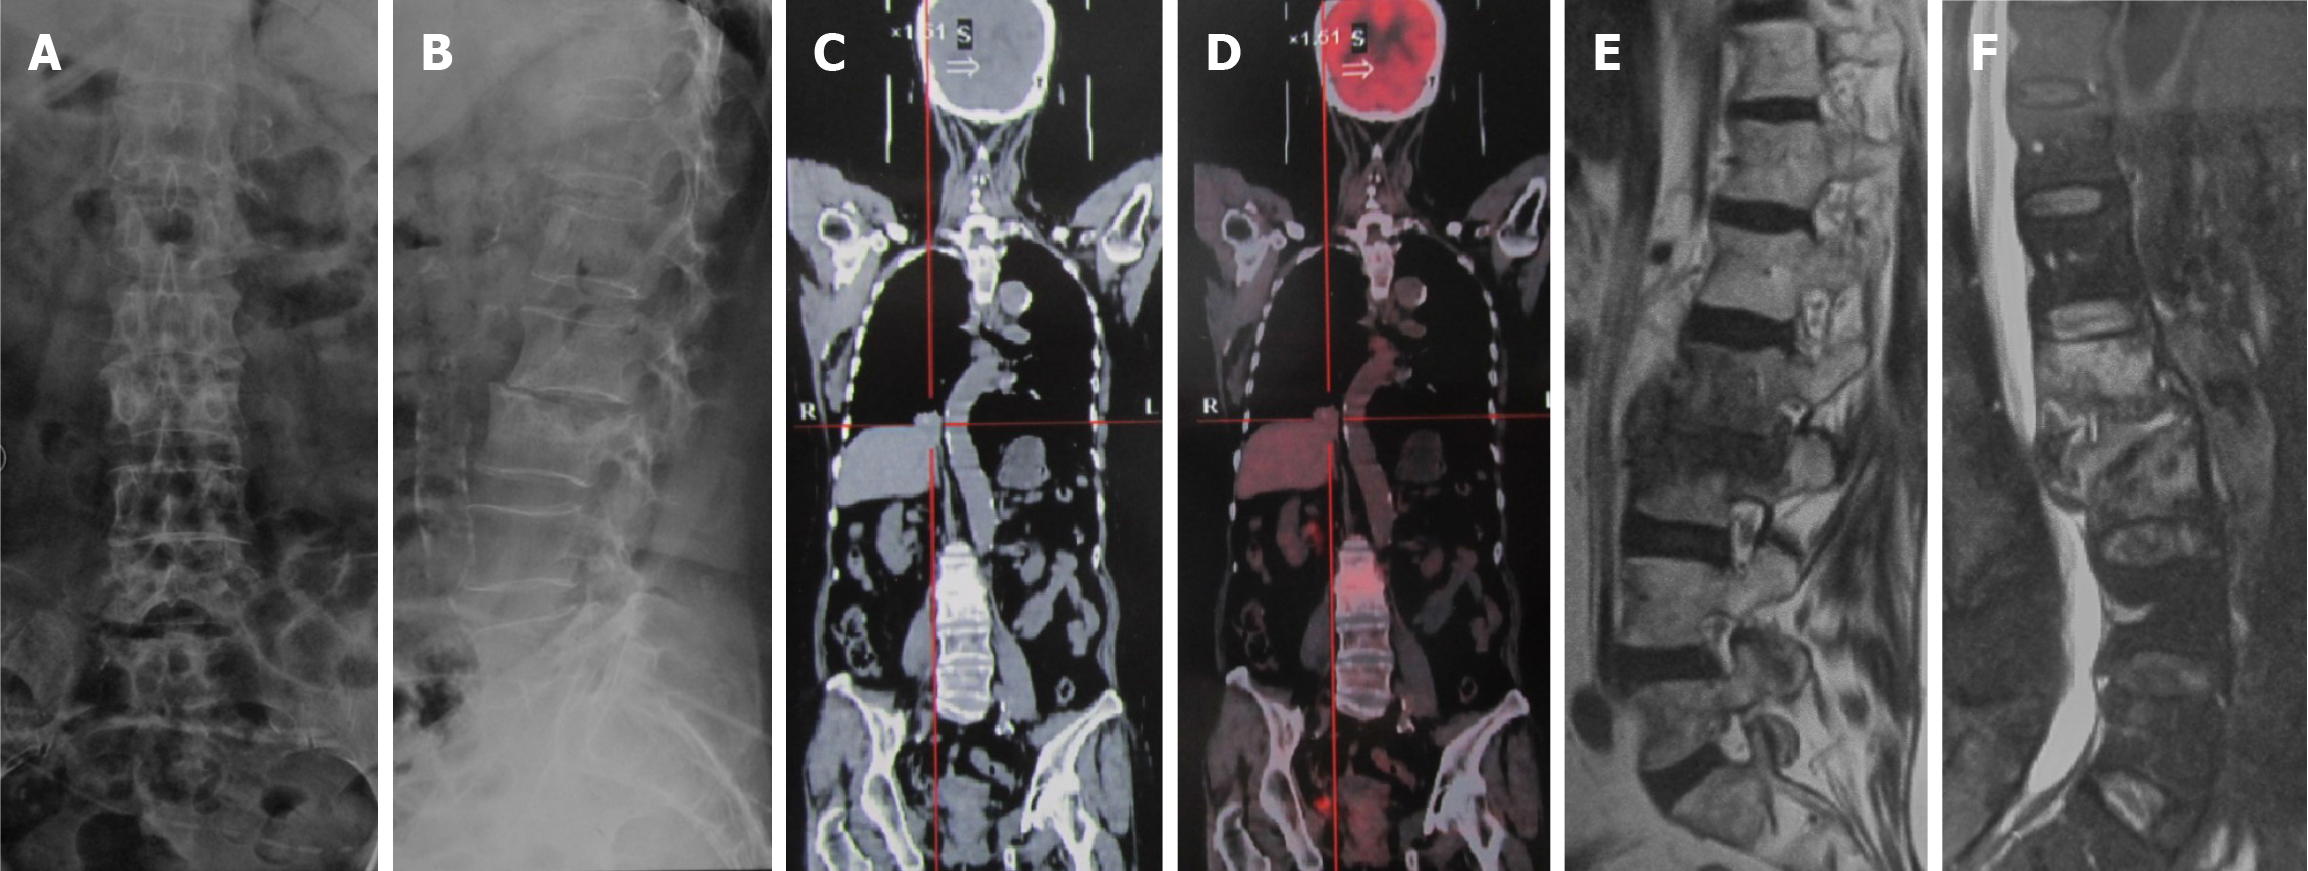

Figure 1 Imaging examinations before surgery.

A and B: Visible destruction of the L2 and L3 vertebral bodies, with narrowing of the L2/L3 space; C and D: Positron emission tomography/computed tomography suggest bone metastasis of lung cancer to the L2 and L3 vertebrae; E and F: Magnetic resonance imaging indicates increased signals in the L2 and L3 vertebral bodies and intervertebral space.